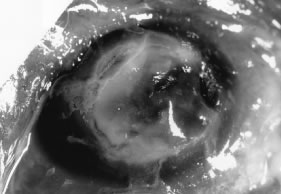

In the early stages of infection, filamentous fungi produce signs that are readily distinguishable from yeast or bacterial keratitis. The most distinctive sign is the presence of delicate, fine, feathery, opalescent, gray-white or yellow-white material in the anterior stroma, surrounded by scant cellular infiltrate or edema (Fig. 1). The epithelium may be intact. The overlying epithelium may be granular and the surface elevated and irregular in contour. Linear infiltrates typically extend into the adjacent stroma. Multiple discrete opacities may develop outside the perimeter of the principal focus of inflammation, either separated by clear stroma or linked by fine linear collections of inflammatory cells and material (Figs. 2 and 3). In the absence of inflammation in the adjacent stroma, branching hyphal fragments may be visualized by biomicroscopy (Figs. 4 and 5). Confocal microscopy may also detect hyphal elements within the stroma.28,29 Peripheral infection resembles noninfectious marginal infiltrative and ulcerative keratitis (Fig. 6). Multifocal keratitis may develop after contact lens wear or injury by multiple projectiles (Fig. 7). In the early stages, iritis is present and the intraocular pressure remains normal. Inappropriate, empirical therapy of fungal keratitis with topical fluoroquinolone or aminoglycoside antibiotics may suppress or eliminate the superficial elements but allow extension of the organisms into the stroma because these agents may possess selective antifungal activity.4,30,31

Fig. 1. Curvularia keratitis (slit-beam illumination). Note the fine feathery infiltrates extending from the central component, minimal cellular infiltrate in the adjacent stroma, and intact epithelium.